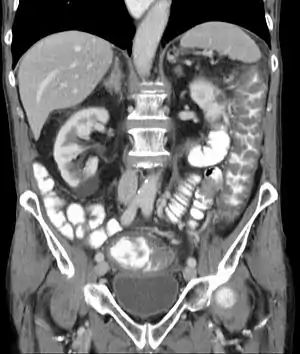

![]() Комп'ютерна томографія живота при псевдомембранозному коліті. Виділяється уражена низхідна частина товстої кишки (Colon descendens) Комп'ютерна томографія живота при псевдомембранозному коліті. Виділяється уражена низхідна частина товстої кишки (Colon descendens) | |

Потовщення кишкової стінки товстої кишки можна побачити при проведенні УЗД та на комп'ютерній томографії. Ендоскопічно спостерігаються світлі відкладення фібрину в товстій кишці, частина з яких плямиста, частина з них злита.